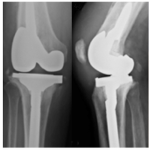

Impacto del grosor rotuliano en una artroplastia de rodilla. Análisis clínico-funcional y complicaciones tempranas

Leonel Pérez Alamino, María Agustina Oláran, Germán Garabano, César Á. Pesciallo